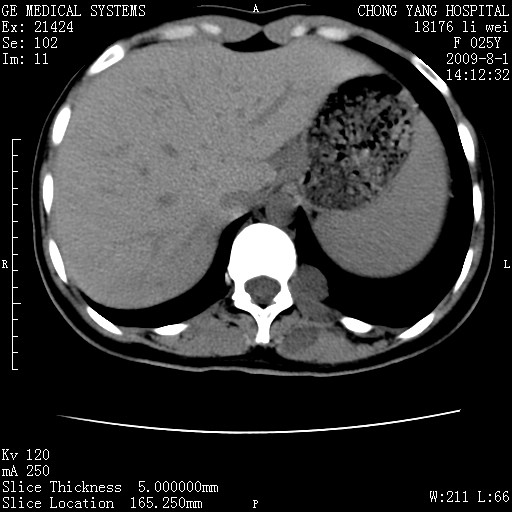

以下是引用pujunzhi在2009-8-1 20:23:00的发言:[br]胸椎旁及背部肌间良性病变,范围广,边界清,沿肌间生长,考虑淋巴管瘤、血管瘤,建议增强扫描。